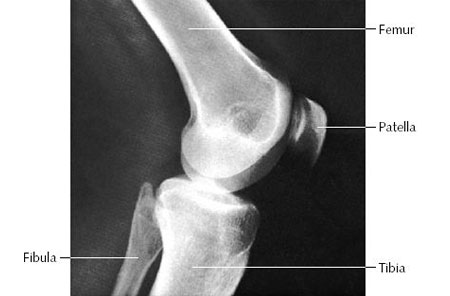

X-rays of the Knee:

These are done to diagnose problems in the bones and or joints

The common types of Knee X-rays a Knee Surgeon would require are

Knee (AP Weight-Bearing View)

Lateral Knee X-rays

Axial View